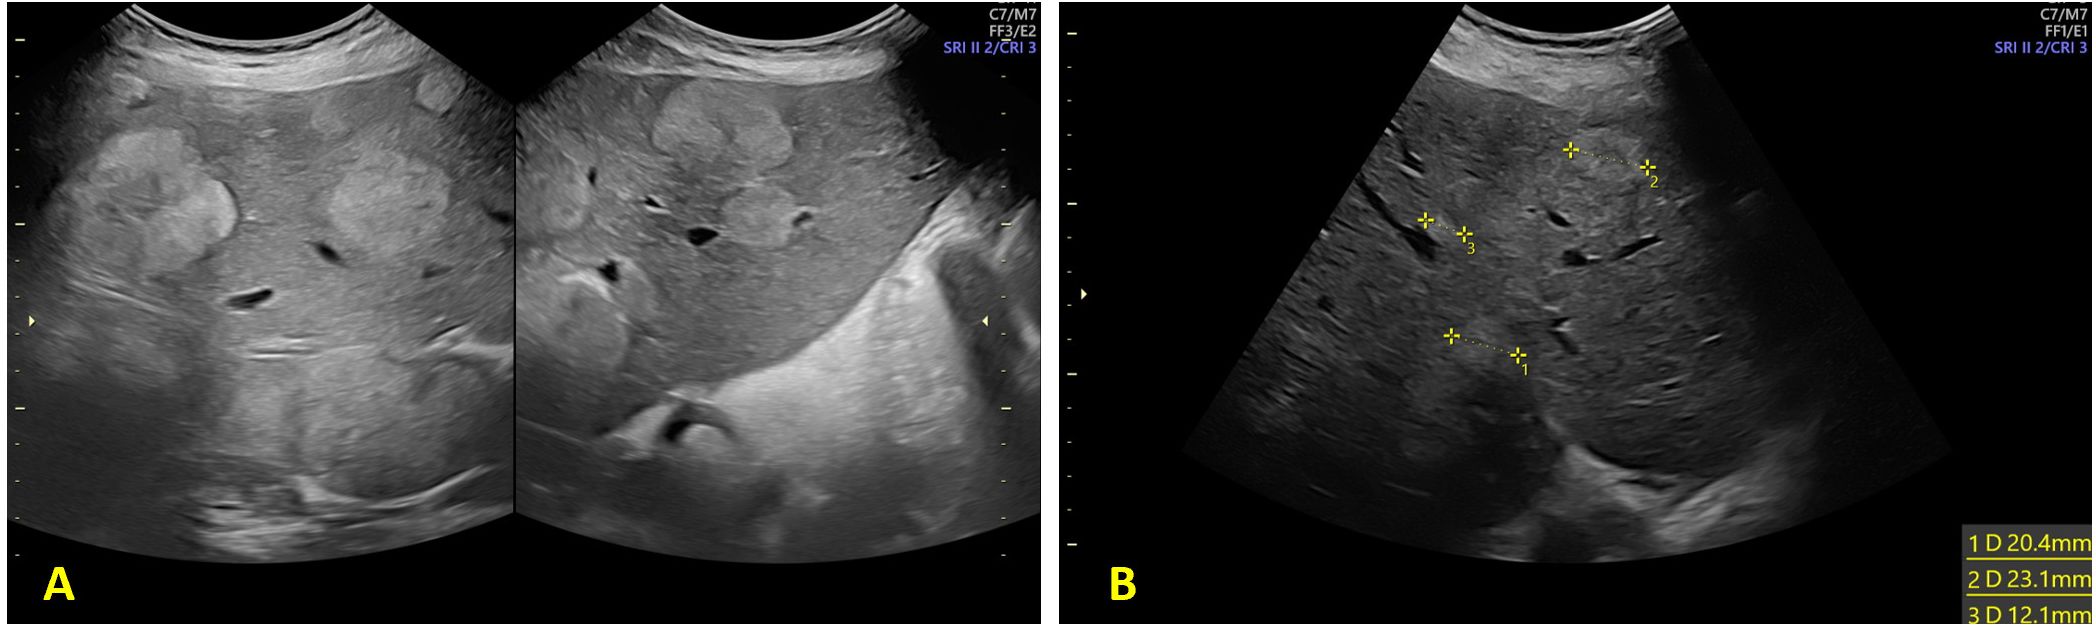

Introduction. Cancer during pregnancy is a rare event and often presents at an advanced stage due to delayed diagnosis. Clinical symptoms are frequently misattributed to normal pregnancy changes, leading to diagnostic challenges. Moreover, concerns regarding fetal safety limit the use of certain imaging modalities and treatment options. Managing cancer in pregnancy requires careful coordination across specialties to balance maternal treatment with fetal preservation. Case-report. We present the case of a pregnant woman diagnosed in the second trimester with advanced metastatic colorectal cancer. The disease involved multiple intra-abdominal sites, and the patient was managed through a multidisciplinary approach. Chemotherapy with FOLFOX scheme was administered during the second and third trimester of pregnancy, leading to a favorable clinical and radiologic response. Delivery was planned at term, with no complications for the newborn. Postpartum oncologic management was continued without delay. Conclusion. This case highlights the importance of individualized care in such complex scenarios and the feasibility and safety of administering chemotherapy during pregnancy.